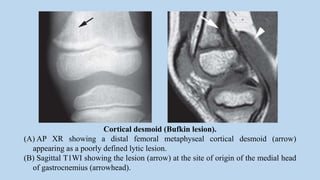

Cortical desmoid (Bufkin lesion).

(A) AP XR showing a distal femoral metaphyseal cortical desmoid (arrow)

appearing as a poorly defined lytic lesion.

(B) Sagittal T1WI showing the lesion (arrow) at the site of origin of the medial head

of gastrocnemius (arrowhead).